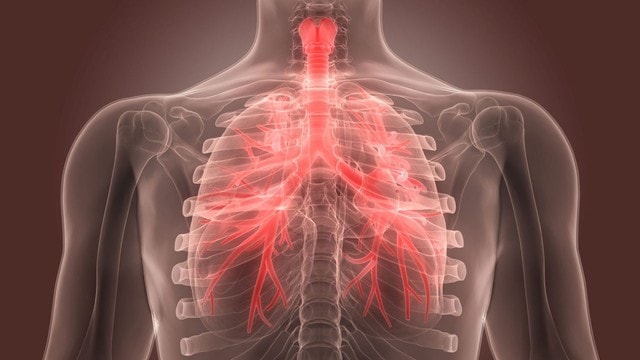

Viêm phế quản cấp là gì?

Viêm phế quản cấp là tình trạng viêm khí phế quản phần lớn là do virus gây ra như Adenovirus, Corona virus, hoặc một số vi khuẩn không điển hình như Mycoplasma pneumonia, Chlamydia pneumoniae. Một số virus cúm A, B cũng là nguyên nhân hay gặp gây bệnh viêm phế quản cấp.Viêm đường phế quản cấp thường lây qua đường hô hấp thông qua giọt bắn, dịch tiết (nước mũi, đờm…) của người bệnh khi ho, hắt hơi, nói chuyện… sau đó người lành hít phải hoặc chạm vào rồi đưa tay lên mũi, miệng.Biểu hiện của bệnh viêm phế quản cấp